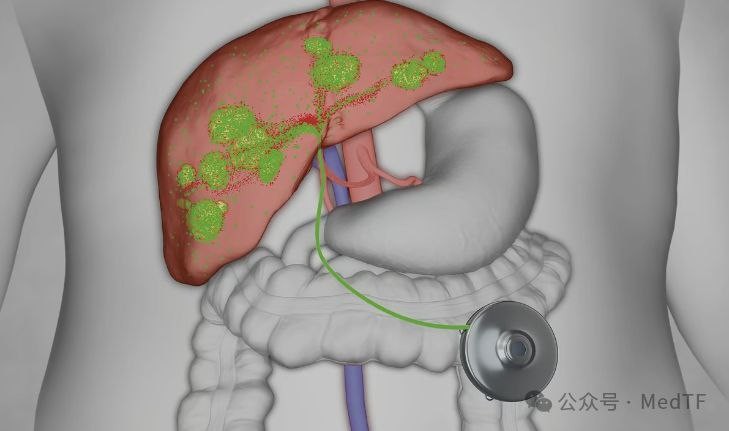

欧洲首个,瓦里安微球

项目类型

器械质押区

起投金额

18000USDT

每日释放:0.9

释放周期:90 天

已购: 7222

剩余: 0